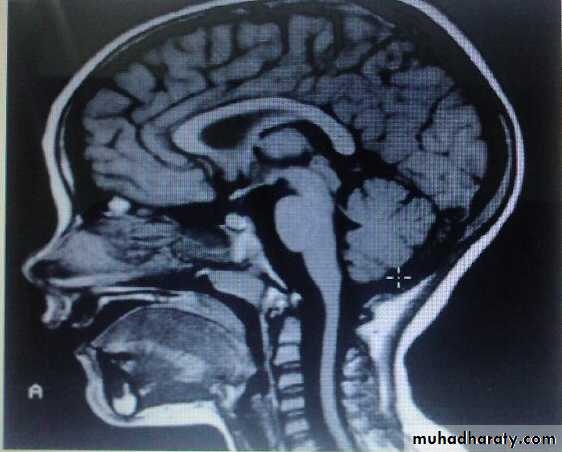

MRI showing spinal cord atrophy in fridrich ataxia